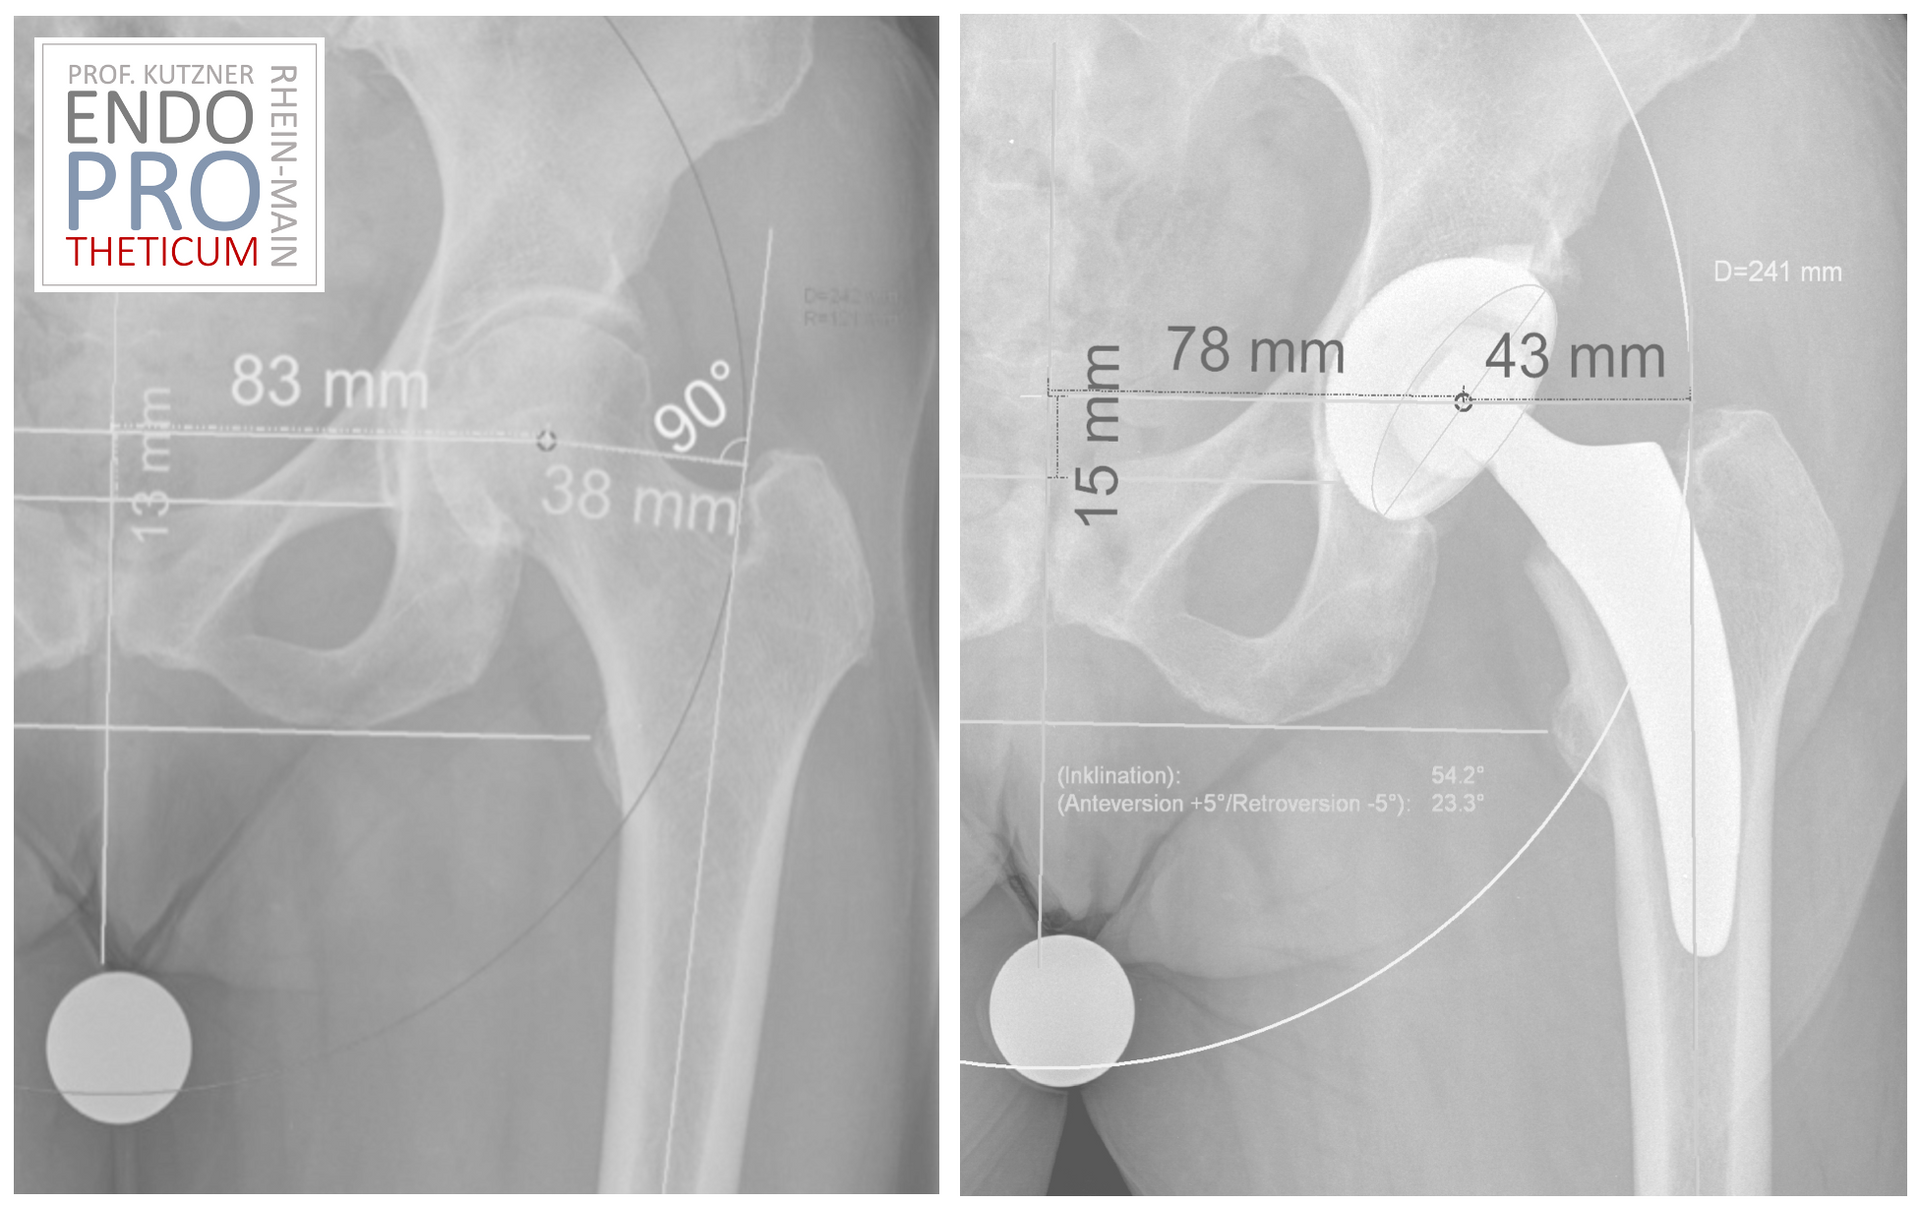

The rise of short-stem prostheses

Short-stem prostheses were developed to overcome some of the problems

conventional implants. Due to their shortened stem length, they offer

they provide better stability and mobility of the hip joint. In addition

they allow for minimally invasive surgical techniques in many cases, resulting in

shorter recovery times and less postoperative discomfort can lead to.